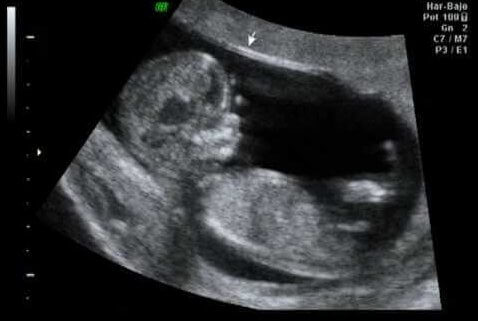

A ecografia na 12ª semana de gravidez

Como ponto alto do primeiro trimestre, a décima segunda semana costuma ser o momento ideal para realizar um exame sobre esta fase da gravidez: na primeira ecografia, se comprova que os órgãos estejam se desenvolvendo da forma correta. Também se verifica o tamanho e peso do bebê, assim como a presença da translucência nucal, o líquido que todos os fetos tem na nuca.

É um momento extremamente importante, já que os especialistas afirmam que entre 60 e 70% dos problemas de má formação que o feto possa apresentar podem ser detectados já nesse momento.

Por outro lado, a espessura da nuca do feto é medida e seu valor é incluído no relatório do primeiro trimestre, o que permite detectar o risco de uma anomalia no número de cromossomos (conhecida como aneuploidias), especialmente a trissomia do par 21 ou a síndrome de Down. Isto se realiza a partir do cruzamento entre esses dados e outros dados que incluem:

- A idade materna.

- Os valores hormonais.

- O valor da translucência nucal.